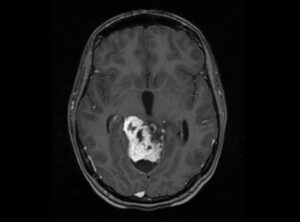

GlioblastomaRadiation therapy (RT) is one of the most common and effective cancer treatments, used in over half of cancer patients. But for some tough cancers, like glioblastoma multiforme (GBM), RT has its limitations. This is because these tumors often have areas with low oxygen (hypoxia), suppress the immune system, resist radiation, and are close to healthy tissue that can’t tolerate high doses.

Traditional radiation tries to give the entire tumor the same amount of radiation, but new research shows that delivering radiation in patterns with high- and low-dose regions—called spatially fractionated radiation therapy (SFRT)—can actually kill tumor cells more effectively and activate the immune system while sparing healthy tissue. One version of this, called minibeam radiation therapy (MBRT), has shown great promise in animals and early human studies.

Several research groups are now exploring combining MBRT with proton therapy (which uses proton particles rather than X-rays) because protons can target tumors more precisely and penetrate deeper without affecting tissue beyond the tumor. However, this combination (pMBRT) is still in early stages of development. One big challenge in treating tumors is their low oxygen levels, because oxygen helps radiation create molecules that damage cancer cells’ DNA. Tumors with little oxygen are much harder to treat. In addition, oxygen levels can affect the immune response and even harm normal brain function when used during anesthesia in radiation treatments.

Researchers in France set out to find out whether pMBRT could overcome the problem of low oxygen, while also maintaining effectiveness against the tumor, supporting immune responses, and avoiding cognitive side effects and healthy tissue damage. They tested this in rats with brain tumors and in healthy animals, to better understand how oxygen levels in the blood influence outcomes. The differential effects of blood oxygenation were assessed by analyzing immune response, survival capability, and histopathological changes in brain and bone tissues.

The study revealed that following pMBRT, no significant influence of oxygen supplementation on survival outcomes or immune infiltration were present. Also, no significant brain or bone tissue alterations were observed, regardless of blood oxygenation levels during irradiation. These findings highlights the promise for pMBRT in glioblastoma treatment compared to CPT and conventional radiation therapy.